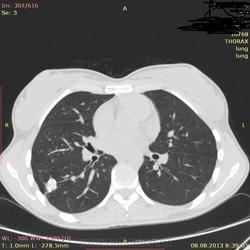

Здраствуйте, коллеги. Нужна ваша помощь молодая девушка 21 г. в течении 2-х лет беспокоит субфибрильная температура, период.гол. боль. В прошлом году сделала ОГК зак: туберкулема. Ей сказали что она перенесла тбс. на ногах, лечение не принимала. Сдавала все анализы без изменении.Родная сестра 3 года назад перенесла тбс.

Туберкулёма в 6-ке.

Распада не вижу, очагов отсева тоже. Контроль и к фтизиатру.

По показанным изображениям данных за активность нет, но без дайкома однозначно не сказать. Посмотрите в MIP при толщине среза 4-6 мм очаги. Если у девушки иммунодефицит любого генеза, то картина даже через несколько дней может кардинально поменяться, так что в любом случае конс.фтизиатра.

Справа в С6 - неправильной округлой формы образование повышенной интенсивности с включениями извести. Данное образование связано с корнем лёгкого бронхо-сосудистой "дорожкой". Рекомендовано анализ мокроты на МБТ!